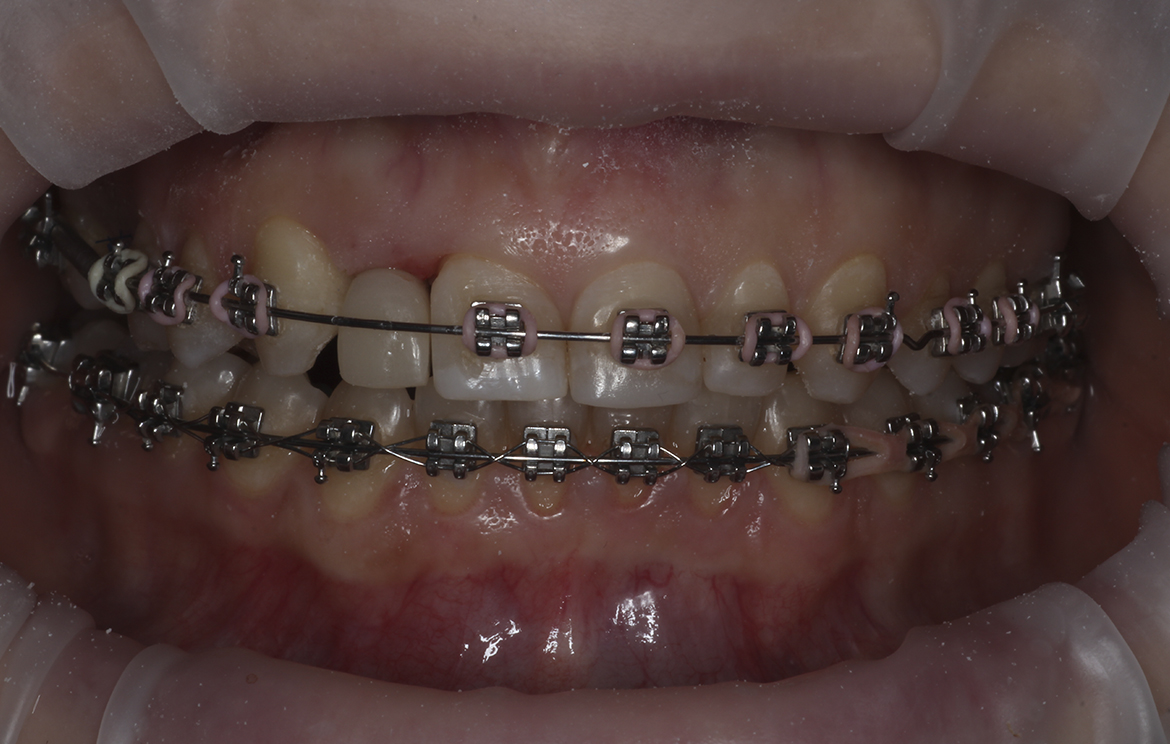

Наши работы